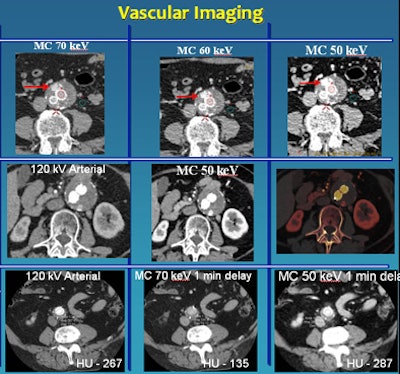

Among their strengths, low-kV scans are "especially popular for vascular imaging because one can exploit the k edge of iodine to gain more attenuation and, therefore, better image quality," Sahani said.

![]() |

| Low-kV imaging improves vascular imaging. Top, middle rows: Endoleak detection is easier on lower-kV images. The CT angiography study was acquired with only 40 mL of IV contrast. Bottom, on delayed-phase acquisition, 50-keV material composition (MC) image provides enhancement and attenuation values similar to arterial-phase imaging. |

The group has traditionally used a three-phase protocol for vascular imaging, but supported by low-kV imaging it's being abandoned in favor of a two-phase protocol that eliminates the unenhanced phase, he said.

The use of so-called "virtual unenhanced images" created from a single late-arterial-phase acquisition may simplify the protocol even further. Moreover, "in select patients we are validating if we can do a late-arterial-phase scan to exploit monochromatic imaging and generate virtual arterial-phase images," he said. "We are exploring that and validating a single-phase acquisition." The experimental protocol delays scanning for only about a minute after contrast injection, and it uses 50 kV to generate the images.

In general, the group has found that 50 kV is optimal for vascular imaging, and 70 kV strikes a nice balance for a combination of vascular and solid visceral imaging, producing good image quality, Sahani said.